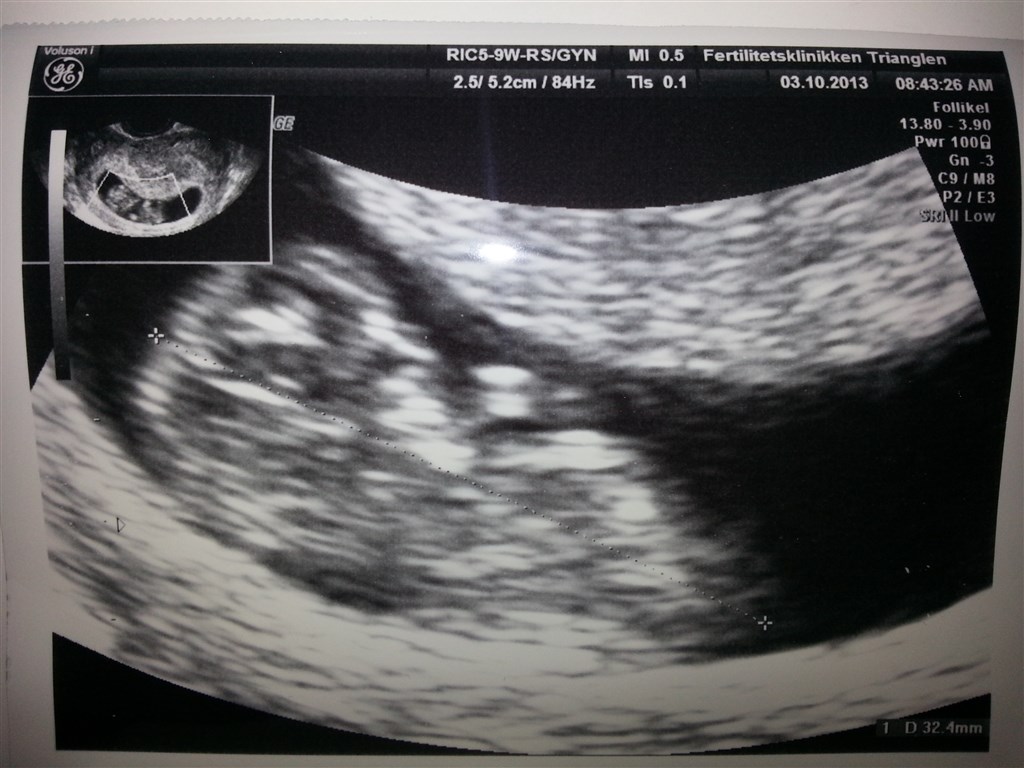

Vi var til kontrolscanning i dag, fordi der var en ekstra tom blommesæk, sidste gang.

Den lille spire har det rigtig godt.

Hjertet banker, der er kommet arme og ben og den bevægede sig også for os. Det var helt vildt at se, at den bevægede sig. Helt helt fantastisk

Så nu er det hele blevet mere virkeligt for os.